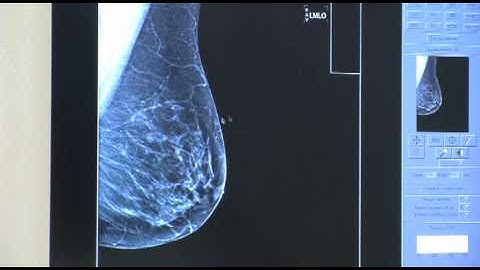

Mass Detection using HIMCAD Mammography CAD system